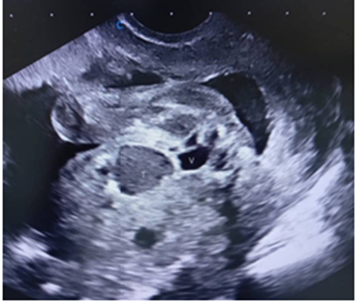

Acudió a la Unidad de Perinatología, realizándose ecografía morfológica del segundo trimestre. Se evidenció en abdomen fetal, por debajo del estómago y adyacente a la vejiga, una imagen hipoecoica de bordes irregulares, que midió 14 x 13 mm, doppler negativo. Se corroboró inserción de cordón umbilical adecuada en abdomen fetal e integridad de la pared del mismo. No se evidenciaron otros hallazgos asociados. Se planteó probable patología gastrointestinal tipo quiste de duplicación intestinal (Figura 1-2).

Figura 1 Ecografía morfológica a las 18 semanas, se observa imagen hipoecoica, irregular que mide 14 x 13 mm (T), vejiga (V).